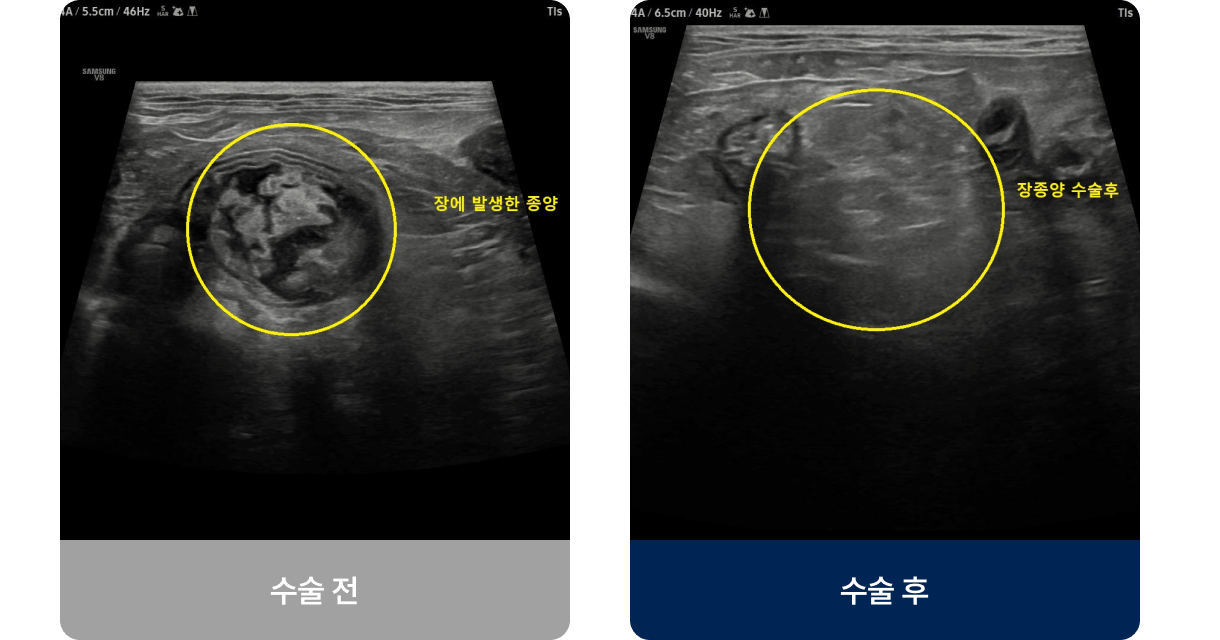

장 속에 이물질(장난감, 뼈, 고무 등)이 걸리거나 종양, 염증 등으로 장의 일부가 막혀 음식물이 통과하지 못하는 상태로, 장 내 순환이 원활하지 못한 경우 탈장 · 복막염 · 장괴사 등 생명을 위협하는 심각한 합병증을 유발할 수 있습니다. 주로 식욕 저하, 구토, 설사 및 대변색의 이상, 복통 증상을 보입니다.

외과적 치료법(수술적 치료)

대상

이물이 크거나 날카로워 배출이 불가능하거나, 장이 완전히 막히거나 괴사·천공 위험이 있는 경우에 시도됩니다.

이물이 크거나 날카로워 배출이 불가능하거나,

장이 완전히 막히거나 괴사·천공 위험이 있는 경우에 시도됩니다.